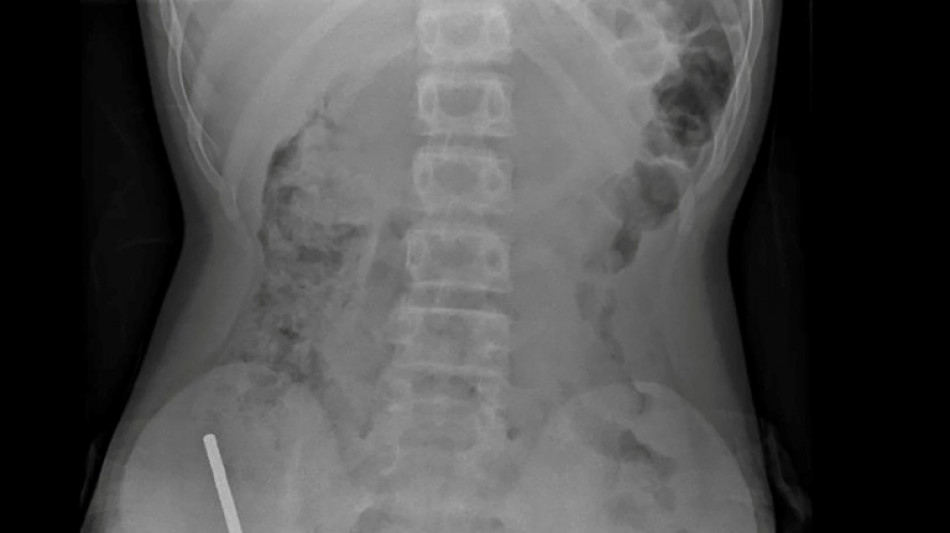

"Il avoué avoir ingéré entre 80 et 100 aimants puissants au néodyme, de 5x2mm environ, une semaine plus tôt", indique un rapport des médecins de l'hôpital de cet hôpital, publié dans le New Zealand Medical Journal (NZMJ).

Les médecins ont déclaré que la pression exercée par les aimants avait provoqué une nécrose dans quatre zones de l'intestin grêle et du gros intestin du garçon.

Il a été opéré afin que l'on lui retire les aimants et les tissus nécrosés, et il a pu rentrer chez lui après huit jours à l'hôpital.